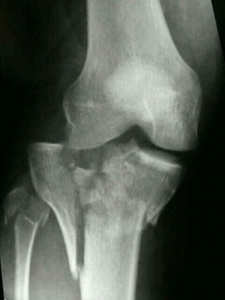

Пациентка П., 46 лет, поступила в клинику РНЦ «ВТО» через шесть дней после бытовой травмы с жалобами на боли в области правого коленного сустава, усиливающиеся при нагрузке, ограничение движений в суставе. Конечность фиксирована задней гипсовой лонгетой, отмечается отечность нижней трети бедра – 3 см, коленного сустава и голени – 5 см (рис. 1).

По рентгенограмме (рис. 1,а) и данным МРТ–исследования (рис. 1, б): полный внутри-суставной перелом С2 с импрессией латерального плато большеберцовой кости.